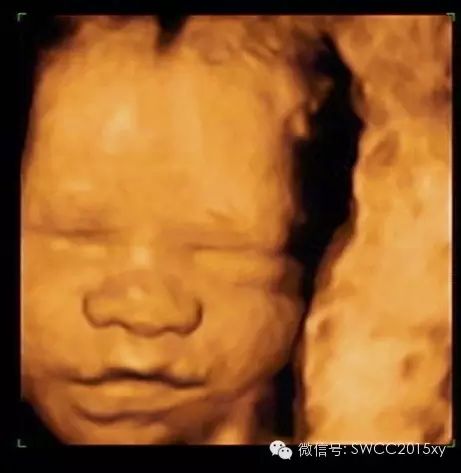

看我皱了一下眉,哦原来我是中国的宝宝,我不是西方的亚当,原来都是妈妈缺钙引起的。因此我们在判断胎儿是否缺钙,不仅仅是看胎儿的长骨的钙化程度和双顶径与股骨的比值,还可以利用现代先进的医学来判断,四维彩超的透明模式来看胎儿的肋骨发育提供更加准确、全面、科学的诊断依据,为减少先天性佝偻病做出应有的贡献。所以准妈妈一定要注意营养、规律、全程、有效补钙哦。